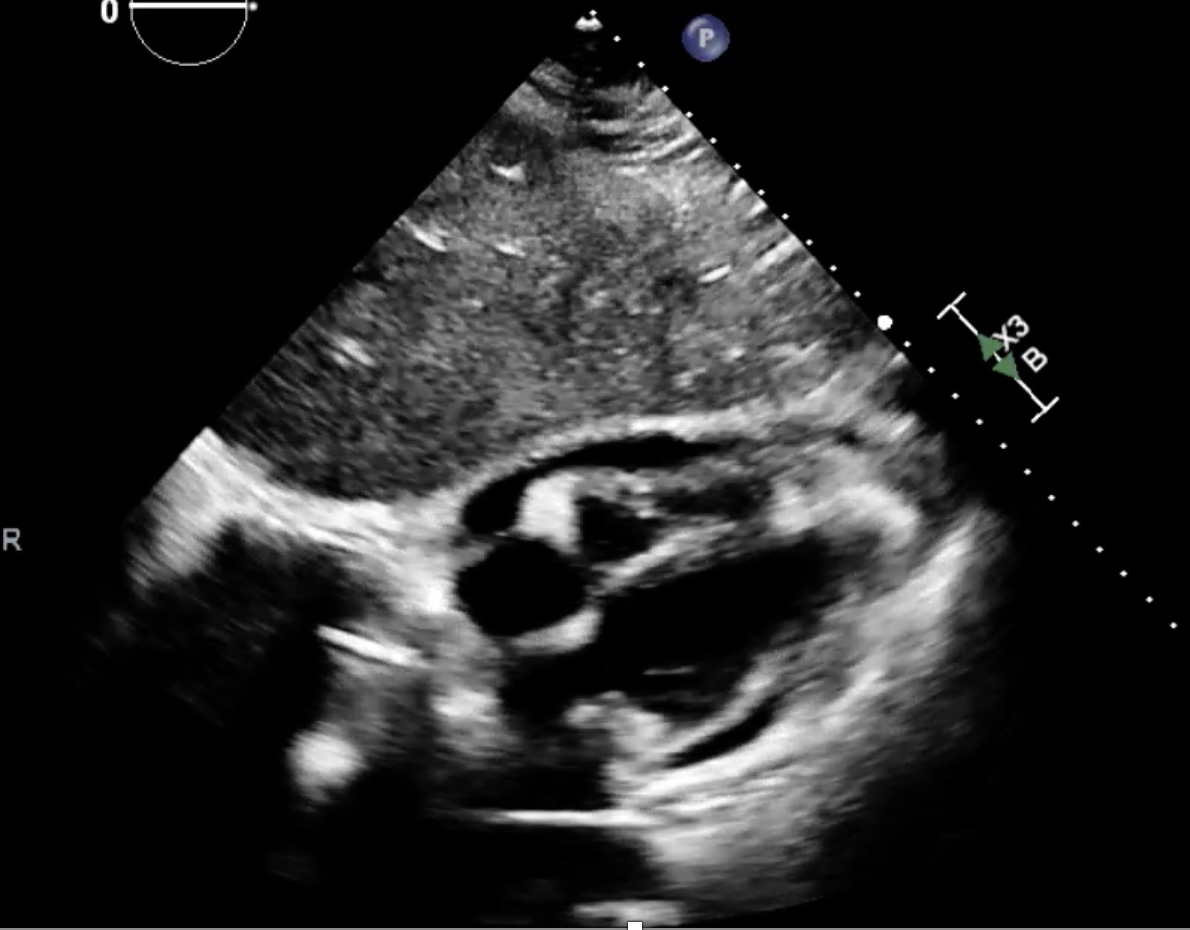

Abstract Body (Do not enter title and authors here): Case Presentation: A previously healthy 33-year-old woman developed acute pericarditis with early tamponade physiology following a Coxsackievirus B infection contracted from her child. Despite urgent pericardiocentesis (550 mL) and standard anti-inflammatory therapy with NSAIDs and colchicine, she progressed to incessant pericarditis necessitating corticosteroids.

Rilonacept was initiated at week 7 due to persistent steroid dependence. Within 4–6 weeks, the patient achieved complete clinical remission, normalization of inflammatory markers, and resolution of echocardiographic abnormalities. Corticosteroids were successfully discontinued over a 3-month taper while maintaining remission on rilonacept at 21-week follow-up.